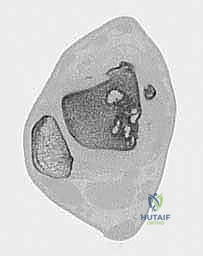

- التصوير بالرنين المغناطيسي (MRI): هو "المعيار الذهبي" لتشخيص آفات الكاحل. يوضح الرنين المغناطيسي بدقة متناهية حالة الغضروف، حجم التكيسات العظمية، ومقدار التورم داخل العظم (Bone marrow edema). من خلال صور الرنين، يحدد الدكتور هطيف أبعاد الآفة (الطول، العرض، العمق) بدقة المليمتر.

- التصوير المقطعي المحوسب (CT Scan): ضروري جداً للآفات الكبيرة. يوفر الـ CT صورة ثلاثية الأبعاد للعظم، مما يساعد الجراح في التخطيط الدقيق لعملية قطع العظم وحجم الطعم المطلوب زراعته.